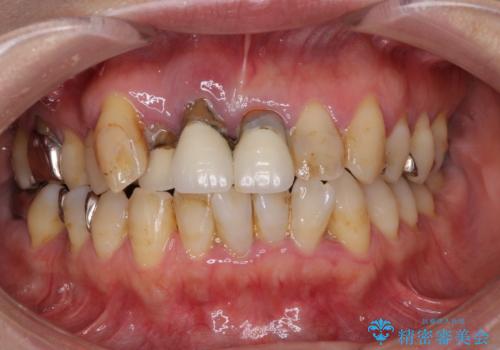

- 左上に装着されている銀歯に違和感があるとの事で来院されました。

レントゲン写真を撮影すると適合の悪いインレーが装着されており、一番奥の歯にはメタルとプラスチック二つの材料が詰められていました。

左上すべてのインレーのやり替えを希望されたため、古い銀歯・虫歯を除去しインレー修復しました。

見た目よりも、適合の良さ、歯に類似した硬さなどの機能面を優先されたためゴールドインレーを装着しました。

一番奥の歯に関しては歯質が少ないためクラウン(被せ物)でのやり替えをすすめましたができるだけ歯の削る量を少なくしたいと希望されたため、アンレー(歯の大部分を覆う詰め物)修復にて治療しました。